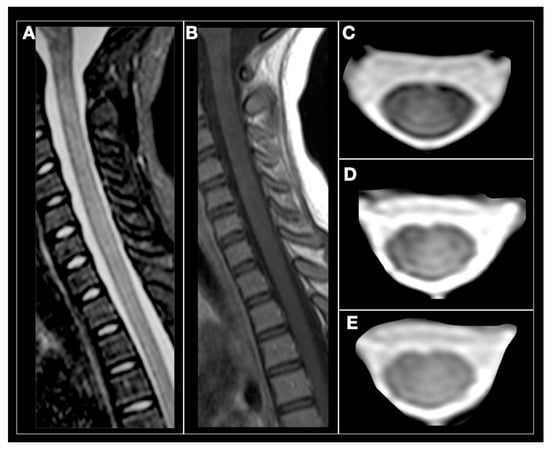

| Spinal cord MRI | Small, peripheral, posterolateral lesions Less than 3 segments Gadolinium enhancement during acute phase | LETM or multiple short segment myelitis Edematous lesions and gadolinium enhancement in acute phase | Central LETM Edematous Necrosis or cavitation Gadolinium enhancement in acute phase | LETM or short myelitis, frequent conus medullaris involvement Linear gadolinium enhancement of the ependymal canal | LETM Central lesions |